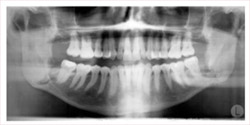

Additionally, we may take digital diagnostic x-rays to reveal any other hidden problems, especially in the areas below the gums. Bitewing x-rays are typically taken every 12 months and a full mouth series of x-rays, is taken every 3-5 years.

Dental X-rays help the dentist visualize diseases of the teeth and surrounding tissue that cannot be seen with a simple oral exam. In addition, X-rays help find and treat dental problems early in their development, which can potentially save you money, unnecessary discomfort, and maybe even your life.

What Problems Can Dental X-Rays Detect?.

- Show areas of decay that may not be visible with an oral exam, especially small areas of decay between teeth

- Identify decay occurring beneath an existing filling

- Reveal bone loss that accompanies gum disease

- Reveal changes in the bone or in the root canal resulting from infection

- Assist in the preparation of tooth implants, braces, dentures, or other dental procedures

- Reveal abscesses (an infection at the root of a tooth or between the gum and a tooth)

- Reveal other developmental abnormalities, such as cysts and some types of tumors